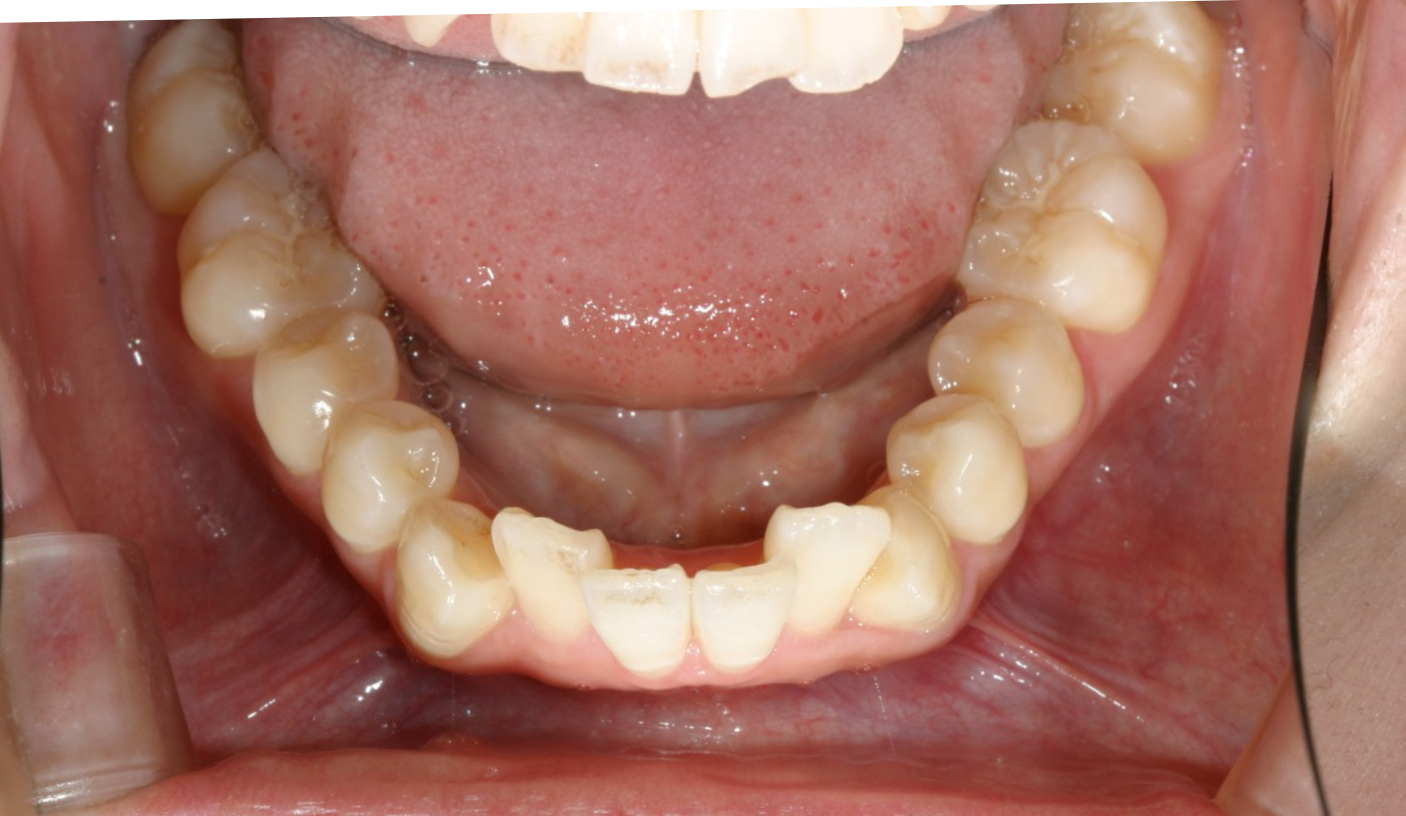

下顎には叢生が目立ちます。